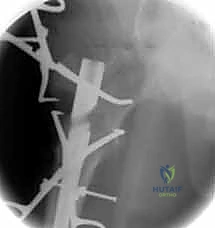

6. التثبيت السفلي (Distal Locking)

لضمان عدم دوران العظمة حول المسمار، يتم إدخال مسمار أو مسمارين صغيرين في الجزء السفلي من المسمار النخاعي عبر شقوق جلدية دقيقة جداً (لا تتجاوز 1 سم).

تُغلق الشقوق الجراحية الصغيرة بغرز تجميلية، وتُغطى بضمادات معقمة. يُنقل المريض إلى غرفة الإفاقة للمراقبة قبل العودة إلى غرفته. العملية بأكملها تستغرق عادة من ساعة إلى ساعتين بفضل خبرة وكفاءة الدكتور هطيف.